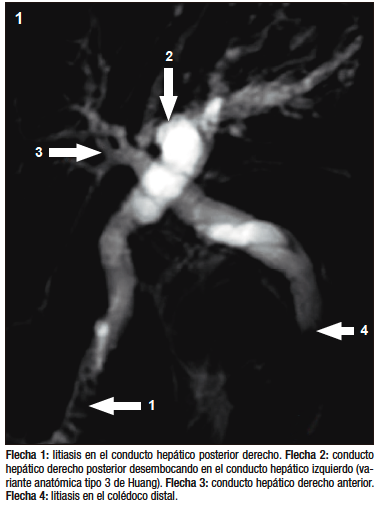

Figura 1. Colangioresonancia magnética

El estudio por colangioresonancia evidenció una variante anatómica biliar tipo 3 de la clasificación de Huang, ya que el conducto hepático posterior derecho drenaba en el conducto hepático izquierdo.1 Se observaron imágenes compatibles con litiasis intrahepática derecha y litiasis en el colédoco distal. La CPRE confirmó la presencia de la variante anatómica del patrón ductal hepático derecho y permitió realizar una canulación selectiva con posterior extracción de litos mediante balón y canastilla.2 El paciente tuvo una buena evolución clínica sin complicaciones.

La clasificación de Huang describe cinco variantes anatómicas del drenaje biliar. En la variante anatómica tipo 3, el conducto hepático posterior derecho drena en el hepático izquierdo. Esta variante, aunque poco frecuente, ha sido informada en 4 a 8% de los estudios por colangioresonancia.1 Su reconocimiento es fundamental debido a que se asocia con un riesgo mayor de lesión quirúrgica y puede dificultar el tratamiento endoscópico.4, 5